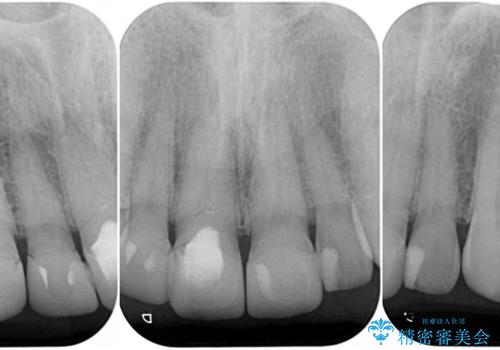

- 前歯のテトラサイクリンによる変色歯と、レジン充填の色の違いを気にして来院された患者様です。

患者様の希望により、前歯6歯をオールセラミッククラウンにて補綴することとしました。